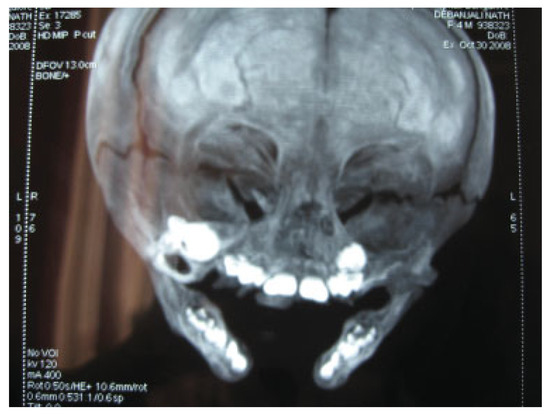

Orbitozygomatic fractures are one of the most common maxillofacial injuries encountered. This study aims to investigate and review the management and complications of orbitozygomatic fractures at the Royal Brisbane and Women’s Hospital (RBWH). Specif...